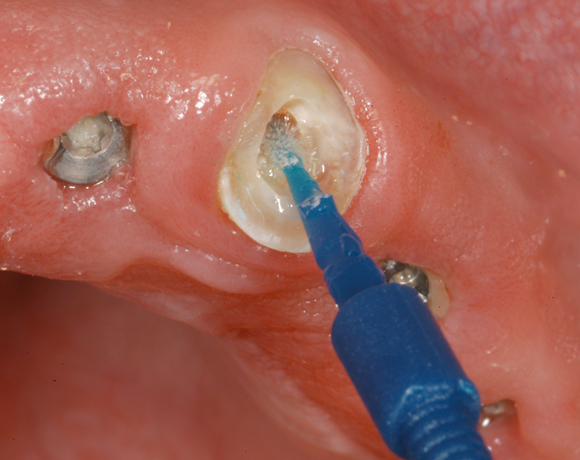

Im nachfolgenden Patientenfall wird ein Zahn mit einem Stift soweit aufgebaut, dass es möglich wird ihn wieder mit einer Krone zu versorgen.